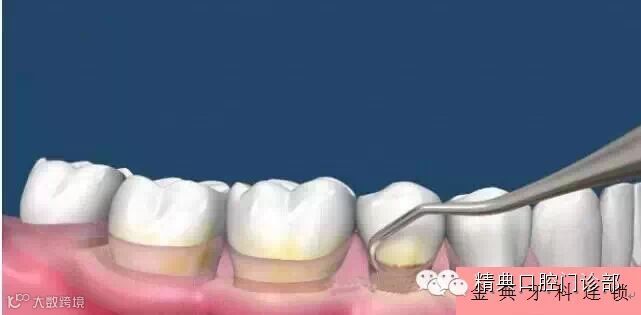

图片十六、牙龈以下的牙结石也应该在洗牙的时候被清除,通常可以采用深部超声洁治法,或者手动龈下刮治法。手动的龈下刮治清洁的效果会更干净一些。

图片十七、用手动的刮治器仔细的刮除牙根面上的牙结石和菌斑以及被菌斑侵蚀的牙骨质表面。

图片十八、龈下刮治后的牙面及牙根光滑,大大降低了牙周袋内细菌的数量。